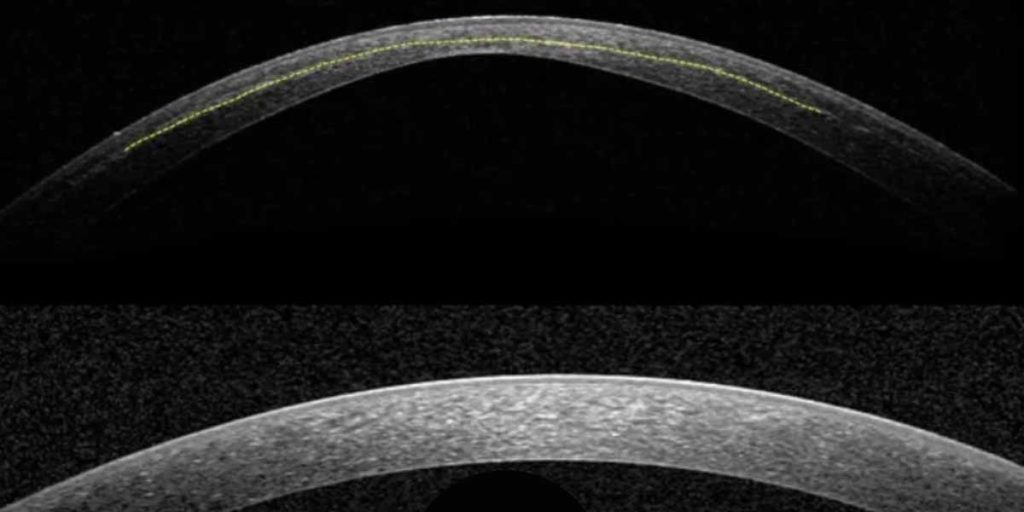

O ponto central desta abordagem é a reticulação individualizada utilizando o protocolo sub400. Em vez de impor uma espessura mínima fixa, o protocolo ajusta o tempo de irradiação UV-A com base na espessura do estroma, mantendo a intensidade de irradiação padrão. Esta estratégia algorítmica modela a interação entre a energia UV-A, a absorção de riboflavina e a difusão de oxigénio, permitindo que a reticulação seja confinada ao estroma anterior, preservando simultaneamente uma margem de segurança endotelial.

Os dados clínicos resumidos na revisão relatam altas taxas de estabilidade tomográfica em córneas finas e ultrafinas, incluindo olhos com espessuras de estroma bem abaixo de 400 µm. Os dados de acompanhamento até dois anos mostram uma estabilização sustentada sem evidência de descompensação endotelial, e uma correlação entre o tempo de irradiação e a profundidade da linha de demarcação apoia a previsibilidade desta abordagem individualizada.